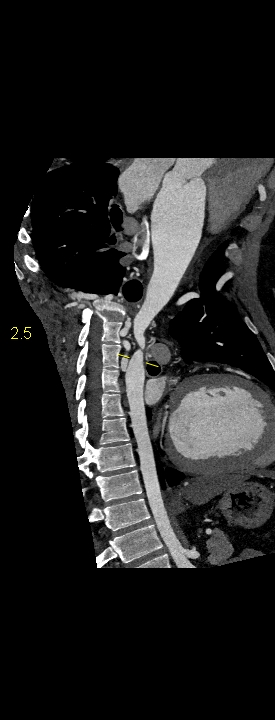

Figurile 1-5: reconstrucții multiplanare din achiziție angioCT aorta toracică

Discuţie caz nr 109: Pacient cu suspiciune de coarctaţie de aortă – are indicație de angioCT aortă toracică; medicul radiolog la acești pacienți este indicat să efectueze investigația cu sincronizare ECG deoarece coarctaţia de aortă poate fi asociată și cu bicuspidie de valvă aortică, mai ales că la acest pacient ecografia cardiacă descria creștere de calibru a aortei ascendențe. Pe reconstrucția cine în planul valvei aortice din achiziția cardioCT cu sincronizare ECG se remarcă o valvă aortică morfologic tricuspidă, funcțional bicuspidă ce asociază ectazie de aortă ascendentă și coarctaţie de aortă descendentă cvasicompletă cu dezvoltare de circulație colaterală intercostală și mamară internă.